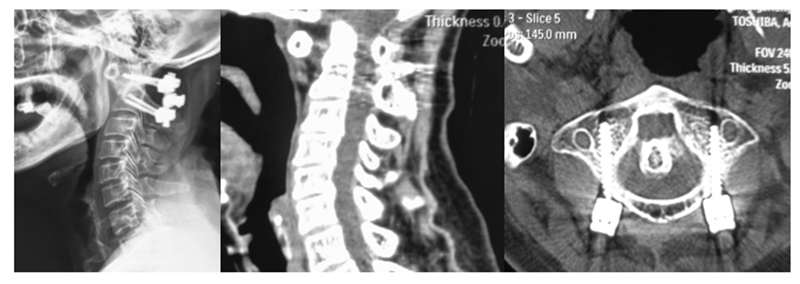

目前治疗AAS及VS主要采取颈椎后路减压植骨融合手术,稳定重建之后炎症反应可有不同程度减轻。但有不少学者观察到在C1-C2融合后,一些RA患者会再次出现下颈椎不稳甚至后凸畸形,严重者可能出现神经功能障碍,往往需要再次手术[6][7][8]。

需要手术医师注意的是,正常男性寰枢椎夹角(atlantoaxial angles, AA angles)为26.7±7°,女性为28.9±6.7°。但术中AA角矫正过大,会导致C2-C7间Cobb角减小。而AA角度过小,又会导致复位效果不理想。

有研究指出,术后理想AA角应维持在20°左右,不必过分矫正。此外,手术医师有时为了避免不融合的情况发生,往往会扩大术中暴露及融合的范围,这可能会导致C2-C3也形成骨性融合,从而引起应力过分集中而导致C3-C4之间失稳[9][10]。

所以,医生在术前应仔细评估手术方案,摆放体位且复位时注意不要过分矫正,并控制暴露范围及保护C2-C3关节突。且术后严密随访,观察患者颈椎曲度变化。对于RA引起的下颈椎不稳,主要以重建稳定,恢复颈椎序列为目的。但术前应认真评估手术方案,若选择行颈椎前路手术,对术中可能出现的出血量增多提前做好预案,术中彻底止血,避免术后出现严重并发症。RA累及腰椎的情况并不多见,但一篇对40例RA患者行腰椎后路融合术的观察发现,其中有15例在术后进行了翻修手术,翻修率高达37.5%。翻修的原因主要有内固定失败,感染,邻近节段退变等。并且有文章指出,RA患者行腰椎融合术后更容易出现邻近节段退变[11][12]。